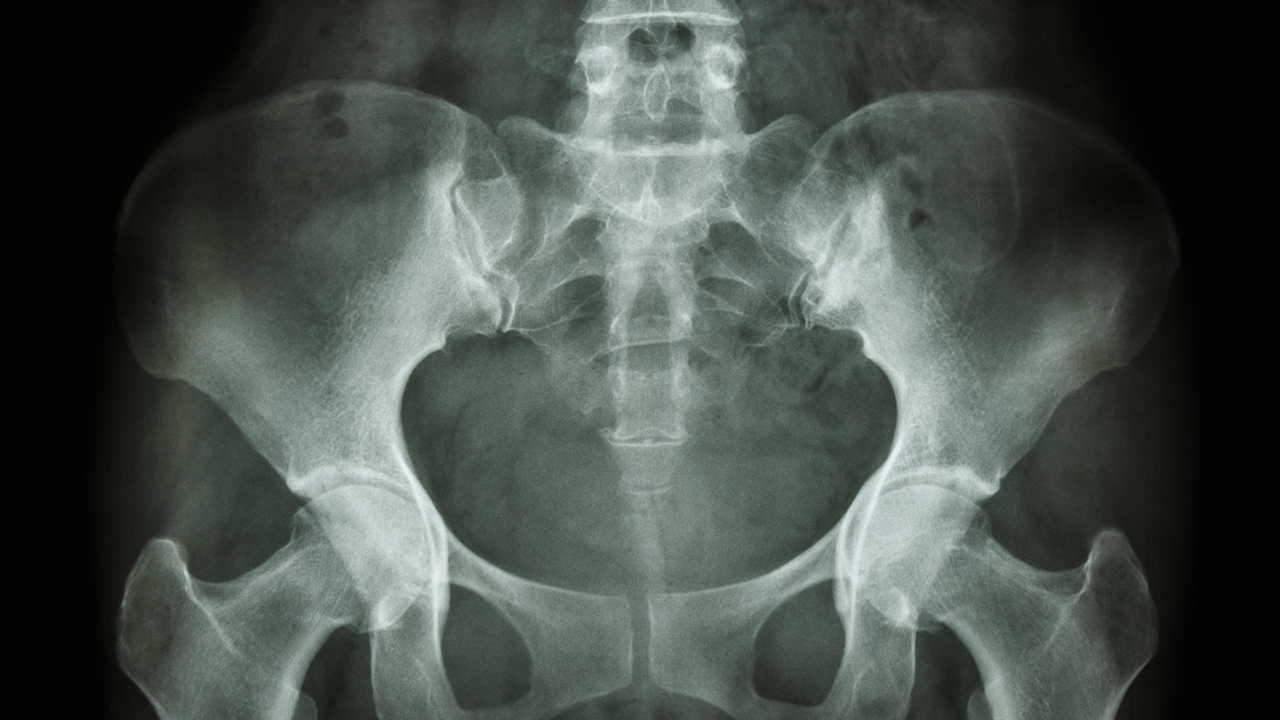

股骨头坏死是一种常见的骨科疾病,主要由长期使用激素、酗酒、外伤等因素导致股骨头血液供应不足,进而引发骨细胞死亡和股骨头塌陷。早期诊断和规范治疗对改善预后至关重要。

股骨头坏死患者在日常生活中需要注意控制体重,减轻关节负担;避免剧烈运动和长时间站立;戒烟限酒,慎用激素类药物;注意保暖,防止受凉;适当进行水中运动等低冲击性锻炼。早期发现症状应及时就医,通过X线、MRI等检查明确诊断,根据病情选择合适治疗方案。定期复查和规范的康复训练对改善预后至关重要。